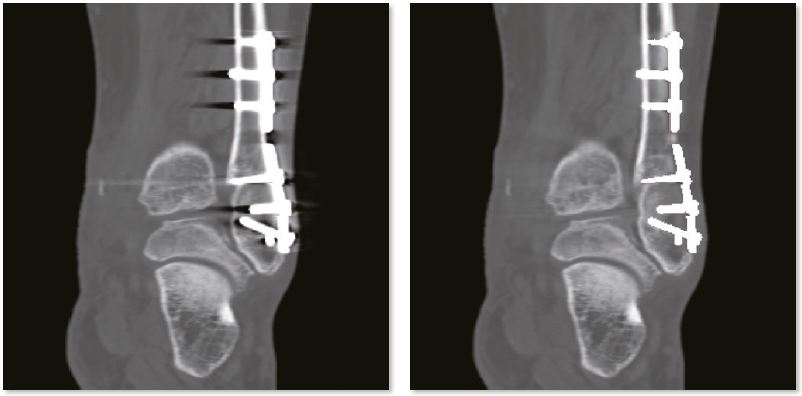

Післяопераційний гомілковостопний суглоб

Зображення SEMAR чітко демонструють перелом малогомілкової кістки. Без SEMAR перелом прихований артефактами, які заважають діагностиці. Крім того, точні положення пристроїв внутрішньої фіксації можна чітко оцінити без артефактів на зображеннях SEMAR.

Звичайне зображення гомілковостопного суглобу

Зображення гомілкостопного суглобу з SEMAR

Звичайне зображення

Зображення з SEMAR